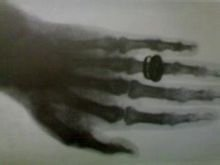

你了解X射线吗?X线是由德国物理学家

威廉·康拉德·伦琴

于1895 年发现的,X 射线具有能够穿过人体,但被骨头和金属等物体吸收的特性。

X射线的发现为人类利用X射线诊断与治疗疾病开拓了新途径,开创了医疗影像技术的先河;

下图为

伦琴本人及其为

妻子拍的一张X光片。